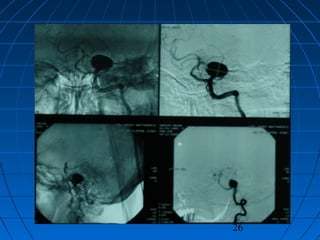

 HP: 53 yaşında kadın hastaHP: 53 yaşında kadın hasta

 Akut, şiddetli başağrısıAkut, şiddetli başağrısı (şiddetli, son 24(şiddetli, son 24

saat içinde)saat içinde)

 GKS 14, Nörodefisit yok (WFNSGKS 14, Nörodefisit yok (WFNS

grade 2)grade 2)

 Fisher grade IIIFisher grade III

CERRAHİCERRAHİ

 Sol suboksipital retrosigmoidSol suboksipital retrosigmoid

yaklaşımyaklaşım

 Anevrizma kliplendiAnevrizma kliplendi